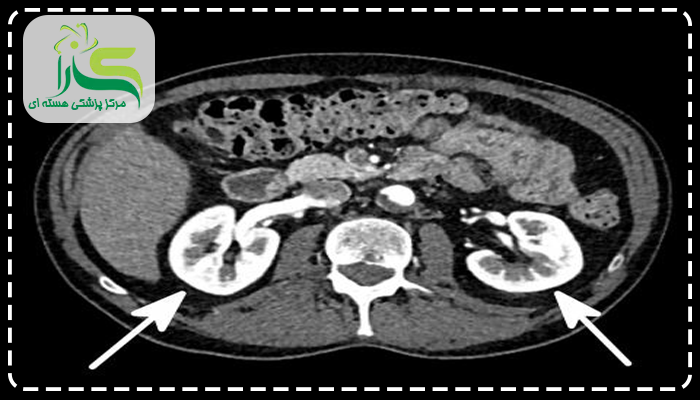

اسکن هسته ای کلیه، که به عنوان اسکن DMSA یا اسکن MAG3 نیز شناخته می شود، یک نوع تصویربرداری پزشکی است که برای ارزیابی عملکرد کلیه ها و تشخیص بیماری های کلیوی استفاده می شود. این روش شامل تزریق رادیودارو به داخل ورید است که توسط سلول های سالم کلیه جذب می شود. سپس با استفاده از یک دوربین مخصوص، تصاویر از کلیه ها گرفته می شود تا توزیع رادیودارو را نشان دهد. در این مقاله از تمام زوایا این موضوع را بررسی کردیم.

اسکن کلیه به دو روش اسکن استاتیک کلیه (DMSA) و اسکن دینامیک کلیه (DTPA) انجام می شود. در ادامه اسکن هستهای استاتیک کلیه (DMSA) را برای شما شرح خواهیم داد.

تجهیزات اسکن هستهای کلیه بهطور عمده شامل یک دوربین گاما و یک سیستم کامپیوتری است. دوربین گاما تشعشعاتی که از بدن بیمار منتشر میشود را شناسایی میکند، که بهصورت تزریقی به یک ورید وارد میشود. این رادیودارو از طریق جریان خون حرکت کرده و در کلیهها متمرکز میشود. دوربین گاما تصاویر کلیهها را هنگام حرکت رادیودارو از طریق آنها ثبت میکند و به ارزیابی عملکرد و ساختار کلیهها کمک میکند. سیستم کامپیوتری این تصاویر را پردازش کرده و تصاویری دقیق و دادههایی برای تشخیص صحیح فراهم میکند. اجزای دیگر ممکن است شامل یک تخت بیمار، مانیتور، و کنسول کنترل برای تکنسین باشد.

اسکن هسته ای کلیه، که به عنوان اسکن DMSA یا اسکن MAG3 نیز شناخته می شود، یک روش تصویربرداری پزشکی است که برای ارزیابی عملکرد کلیه ها و تشخیص بیماری های کلیوی به کار می رود. این روش شامل تزریق رادیودارو به بیمار و سپس تصویربرداری از کلیه ها برای مشاهده توزیع رادیودارو است. اسکن هسته ای کلیه می تواند برای تشخیص طیف وسیعی از بیماری های کلیوی، از جمله عفونت کلیه، انسداد کلیه، تومورهای کلیه و مشکلات مربوط به پیوند کلیه مفید باشد. این روش اطلاعات دقیقی در مورد عملکرد هر کلیه به صورت جداگانه ارائه می دهد.